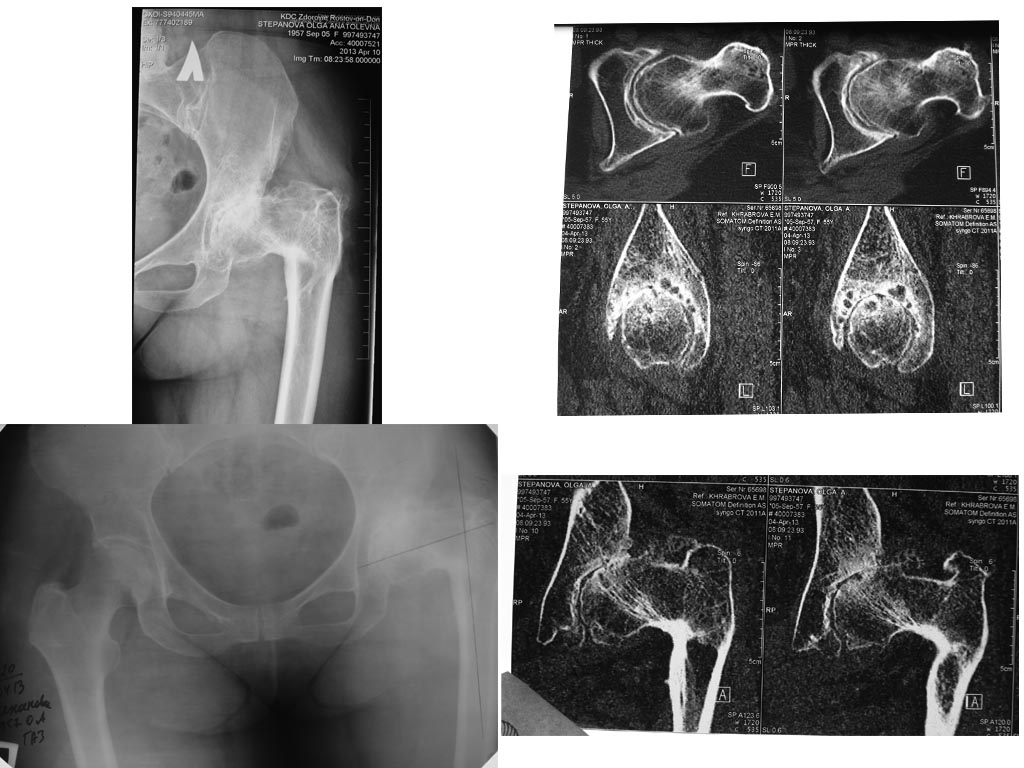

Здравствуйте, коллеги! Поделитесь, пожалуйста, своими мыслями в отношении представленного случая. Даме 56 лет. В 11 лет ей была выполнена варизирующая остеотомия проксимального отдела бедра в связи с дисплазией левого тазобедренного сустава. В настоящее время: Жалобы на боль (5 баллов по ВАШ), ограничение движений в левом т/б суставе (обективно: сгибание до 150 град, отведение 20 град, ротация 20), укорочение (приблизительно 8 см). Желает эндопротезирование.

Предложение: для начала выполнить удлинение "на гвозде" на 4-5 см (остеотомия на уровне дистальной трети), затем - говорить об эндопротезировании.

Обоснование: 1) удлинить при эндопротезировании на 8 см не представляется возможным из-за ригидности мышц и сухожилий; 2) высокой вероятности вывиха эндопротеза после осуществления релиза тазобедренного сустава; 3)вероятность тракционного повреждения седалищного нерва.

Удлинять ничего не надо - получите непрогнозируемое протезирование. Скорее может понадобиться укорачивающая остеотомия. Длинна компенсируется за счет коррекции ШДУ и устранения сгибательной и приводящей контрактуры (обязана быть при такой картинке) не надо гоняться за этими 8 см, корее всего это ортопедическое укорочение. Длинны после операции ей хватит, учитывая длительный анамнез, более того - после операции, даже с укорачивающей остеотомией, ей будет казаться первое время, что нога избыточно длинная

Согласен с мнением Максима. Укорочение 8 см - функциональное, а анатомическое не более 4-5 см. Без особого риска можно провести первичное протезирование. Для перестраховки можно воспользоваться рекомендациями Лазарева АФ. В ряде случаев мы использовали предварительное низведение АВФ (высокие врожденные вывихи бедра). Ни в одном случае не получали нейропатий. АИФ